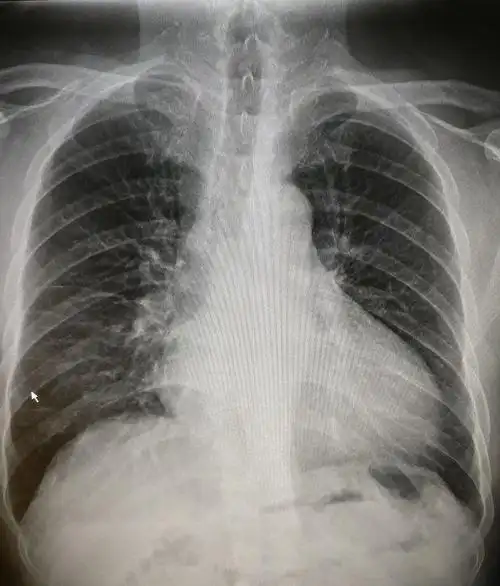

没想到做胸片就发现肺小结节,经过进一步诊断,考虑是肺癌,今天微创